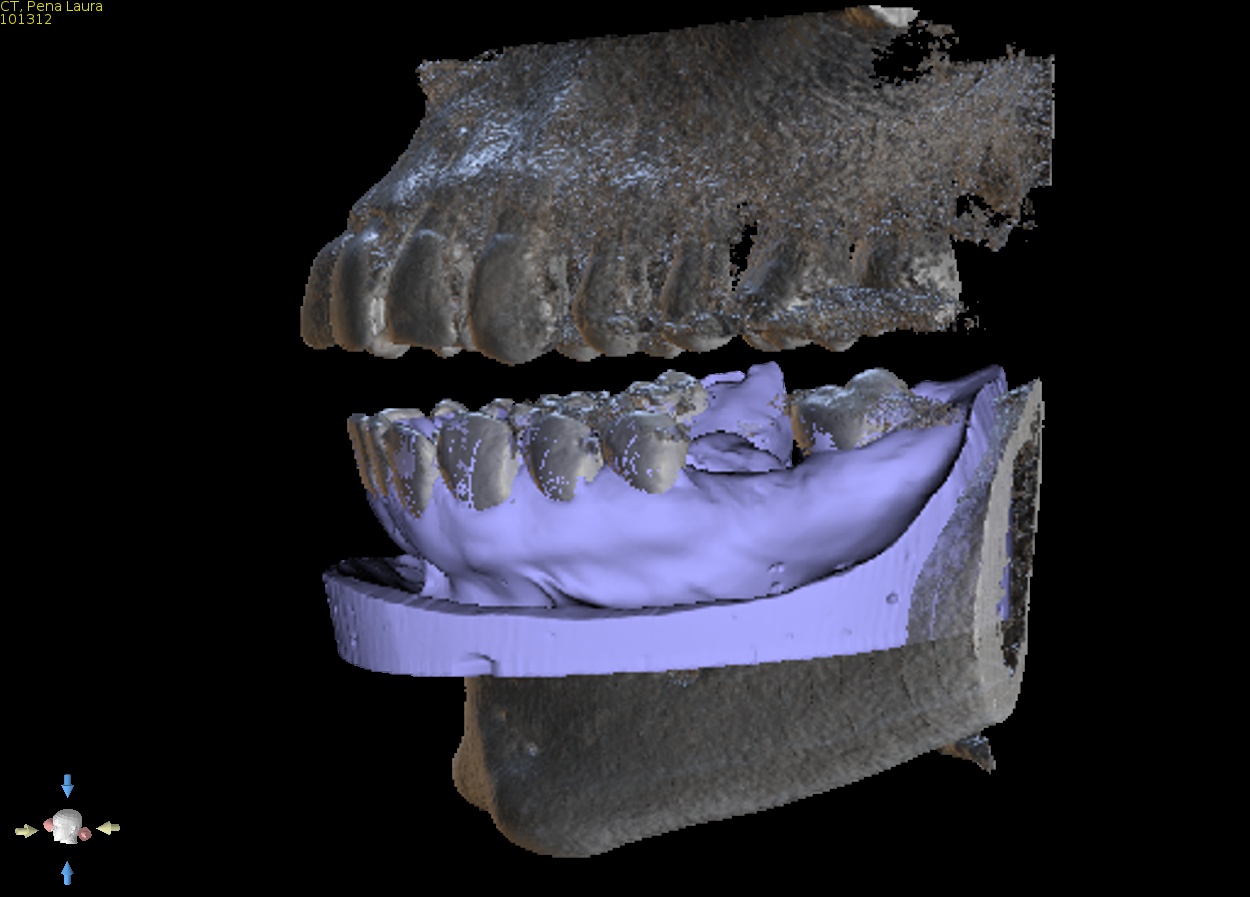

2. Virtual implant placement

Supply us with the implant brand and size and we will position it exactly to your specifications and in relation to the virtual final tooth position. We will send a written report for you to check and note any changes if needed. We will not make the guide until you are 100% satisfied with the virtual placement. Alternatively use free software to plan the case yourself and send us the plan file and we can make the guide from that.